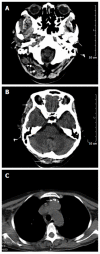

Blue rubber bleb nevus syndrome (BRBNS) is a rare disease characterized by multiple venous malformations and hemangiomas in the skin and visceral organs. The lesions often involve the cutaneous and gastrointestinal systems. Other organs can also be involved, such as the central nervous system, liver, and muscles. The most common symptoms are gastrointestinal bleeding and secondary iron deficiency anemia. The syndrome may also present with severe complications such as rupture, intestinal torsion, and intussusception, and can even cause death. Cutaneous malformations are usually asymptomatic and do not require treatment. The treatment of gastrointestinal lesions is determined by the extent of intestinal involvement and severity of the disease. Most patients respond to supportive therapy, such as iron supplementation and blood transfusion. For more significant hemorrhages or severe complications, surgical resection, endoscopic sclerosis, and laser photocoagulation have been proposed. Here we present a case of BRBNS in a 45-year-old woman involving 16 sites including the scalp, eyelid, orbit, lip, tongue, face, back, upper and lower limbs, buttocks, root of neck, clavicle area, superior mediastinum, glottis, esophagus, colon, and anus, with secondary severe anemia. In addition, we summarize the epidemiology, clinical manifestations, diagnosis, differential diagnosis and therapies of this disease by analyzing all previously reported cases to enhance the awareness of this syndrome.